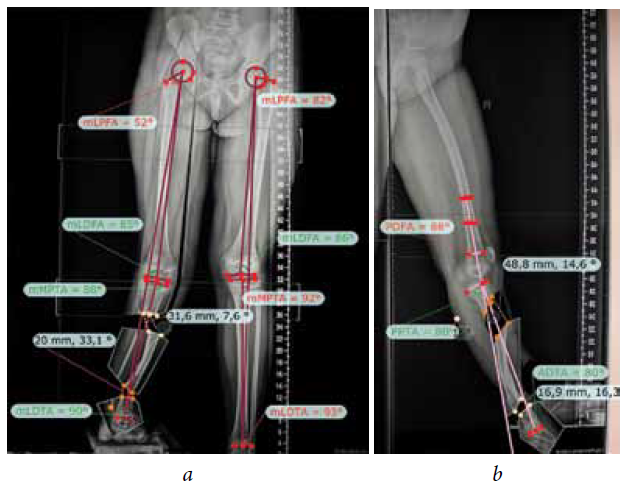

The second stage of treatment was the recommended correction of the resulting multiplane deformities of the affected lower extremity (mMPTA was 94°, mLDTA was 71°, aPPTA was 90°, and aADTA was 59°, shortening the affected lower limb by 8.0 cm). For lengthening and deformity correction of the right lower limb, the patient underwent preoperative planning for deformity correction with the exception of osteotomies in the area of consolidated pseudoarthrosis at the age of 9 years. According to the plan, a two-level osteotomy of the shin bones was performed, as along with lengthening by 5 cm by the Ilizarov method. The deformity was corrected using a repositional unit with Ortho-SUV computer navigation properties. The period of deformity correction was 58 days, and the external fixation period was 247 days. At the end of the fixation period, a recurrence of deformities of the tibial bones was detected with the formation of a deformity apex at the level of the proximal and distal tibial growth zones (mMPTA was 94°, mLDTA was 82°, aPPTA was 86°, and aADTA was 80°) (Fig. 1–4). We applied hemiepiphysiodesis to correct the recurrence of valgus deformity of the tibia. The period of deformity correction was 269 days. The reference angles values of the tibia were within the accepted ranges.

Fig. 3. Preoperative planning for deformity correction in a patient with cCPASB using specialized software: а — anterior-posterior view; b — lateral view

Fig. 4. Roentgenograms of the patient with cCPASB following deformity correction of the bones of the right tibia: а — anterior-posterior view; b — lateral view